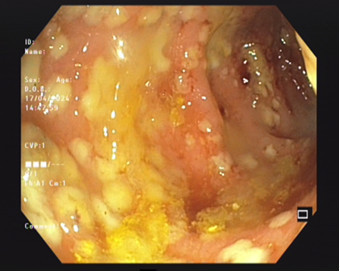

Các bác sỹ cho biết, cụ H bị mất nước nặng, rối loạn điện giải và suy thận cấp. Sau khi đánh giá tiền sử bệnh và tình hình người bệnh, Ekip bác sỹ của khoa đã nhanh chóng cấp cứu, bù nước điện giải và tiến hành nội soi đại tràng cho cụ. Hình ảnh nội soi cho thấy niêm mạc đại tràng của cụ bị viêm trợt, phù nề mạnh, có rất nhiều giả mạc trắng bám trên bề mặt.

| Hình ảnh viêm đại tràng giả mạc qua nội soi của bệnh nhân - Ảnh BVCC |

Qua kết quả nội soi và khai thác thông tin từ gia đình, các bác sỹ khoa Nội Tiêu hoá nhận định: trường hợp của cụ H là trường hợp điển hình của bệnh Viêm đại tràng giả mạc do dùng thuốc kháng sinh bừa bãi. Khi dùng quá nhiều loại kháng sinh trong thời gian dài sẽ làm mất các vi khuẩn có lợi ở ruột, vi khuẩn có hại (vi khuẩn C. Difficile).phát triển mạnh gây viêm đại tràng.

Độc tố tác động vào niêm mạc đại tràng gây viêm và tăng bài tiết tạo thành giả mạc màu trắng. Giả mạc này mềm, dễ bong và khi bong ra sẽ để lại viêm, loét và gây chảy máu niêm mạc.